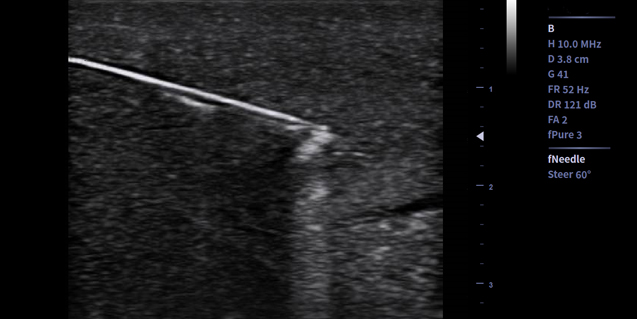

微血流技术 Micro Flow

- 微血流成像技术基于时间,空间和参数信息共同检测血流,可提高对低速血流的灵敏度,有效抑制非血流信号的干扰

临床图像